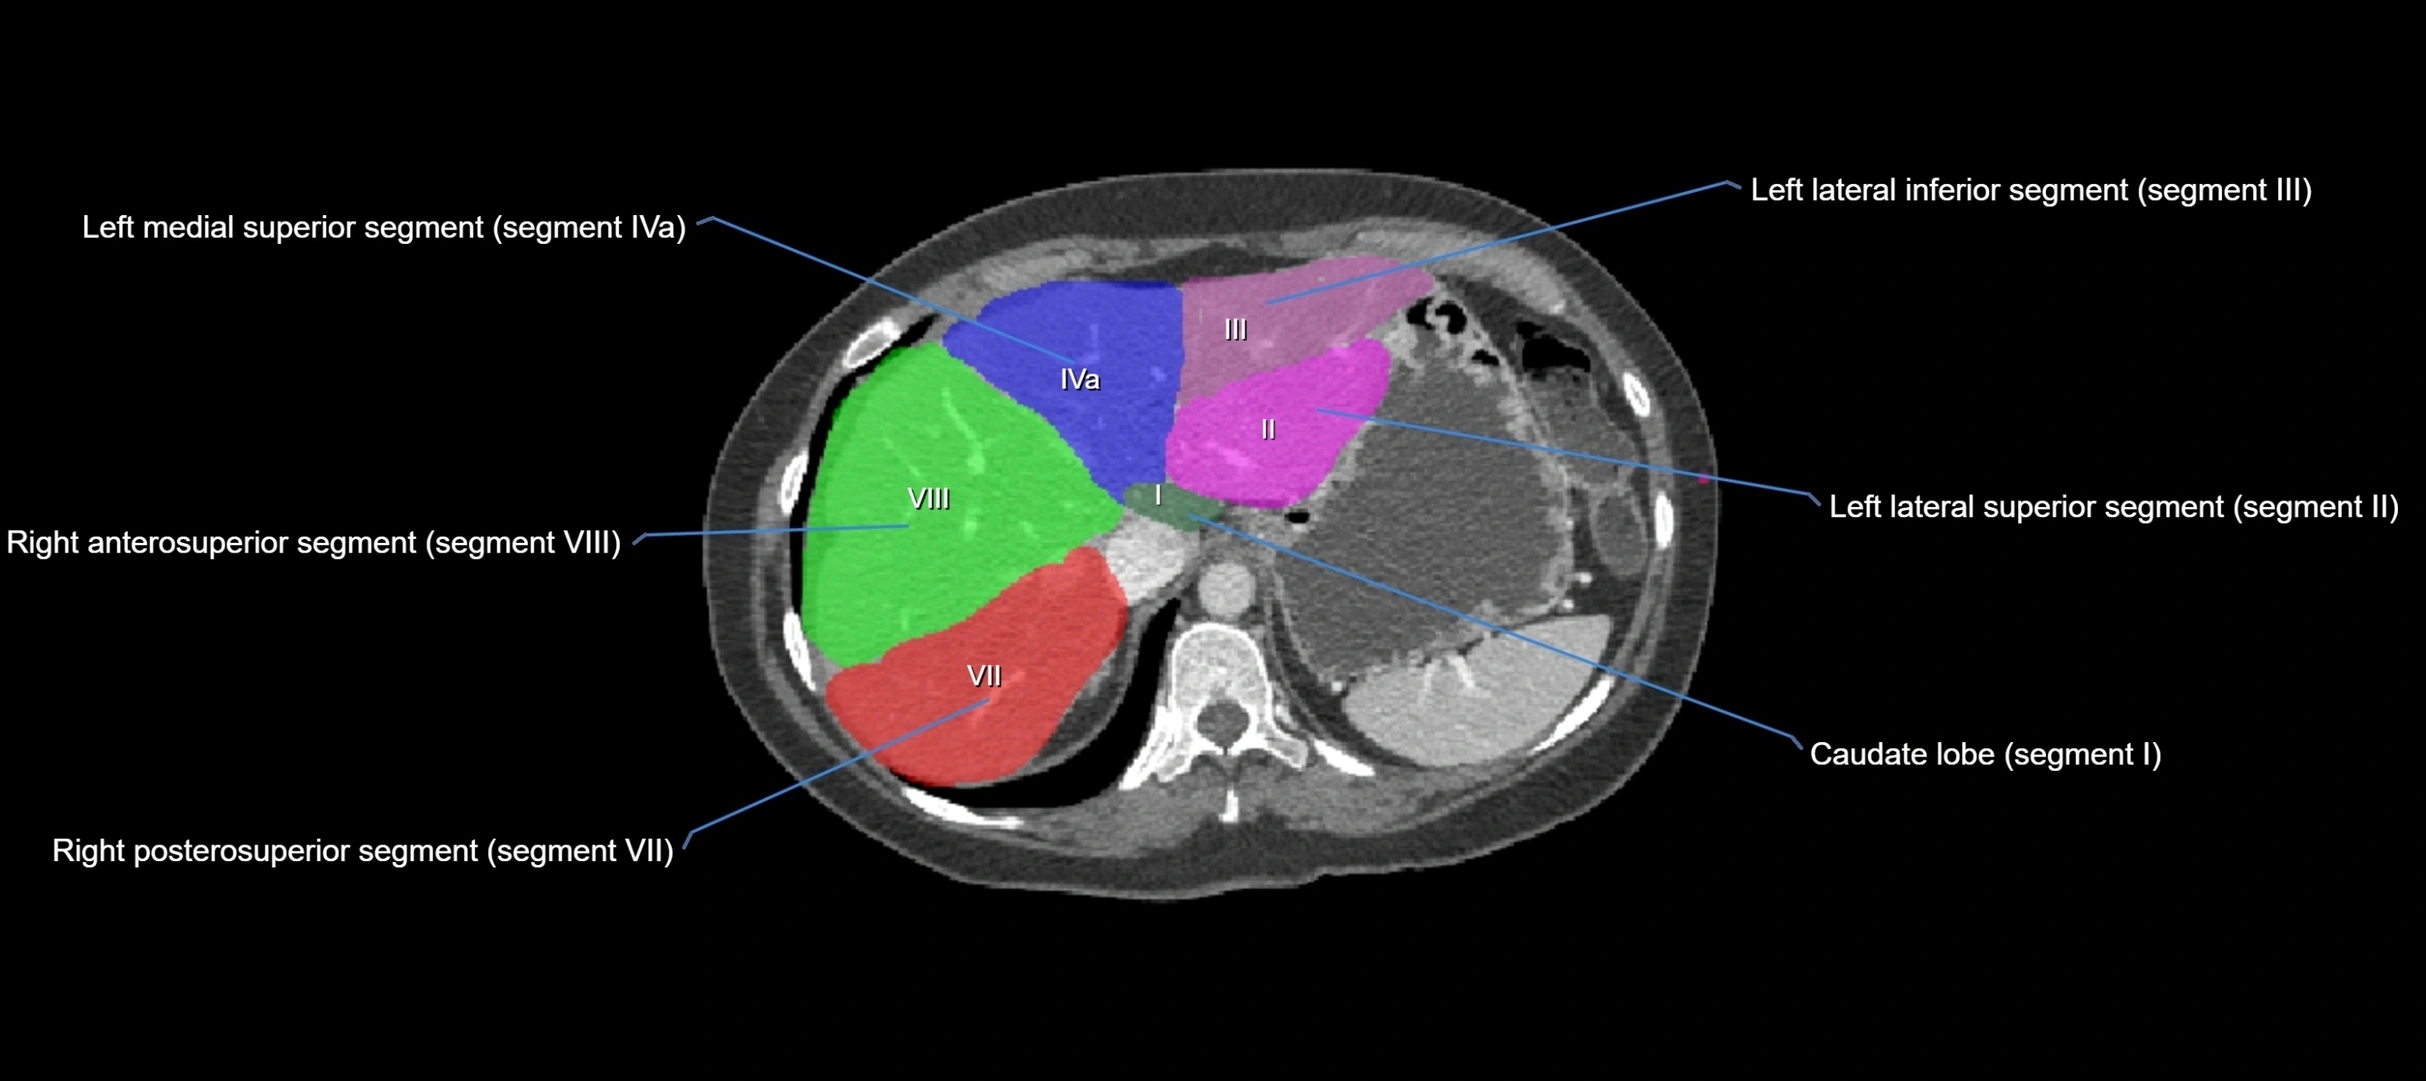

The caudate lobe of the liver is a distinct anatomical subdivision of the liver, designated as segment I in Couinaud’s classification. It lies on the posterior surface of the liver, between the fissure for the ligamentum venosum (left boundary) and the groove for the inferior vena cava (IVC) (right boundary). Superiorly, it is related to the posterior liver surface, and inferiorly it is separated from the left lobe by the porta hepatis.

The caudate lobe is unique because it receives dual portal venous and arterial inflow from both the right and left portal veins and hepatic arteries. It also has independent venous drainage directly into the IVC via multiple small hepatic veins, unlike other lobes that drain through the three main hepatic veins.

CT Image

image